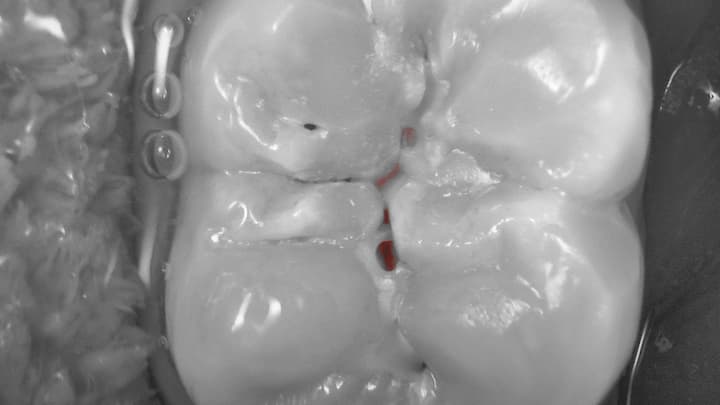

Cario mode

Wykrywanie próchnicy za pomocą diod LED metodą fluorescencyjną.